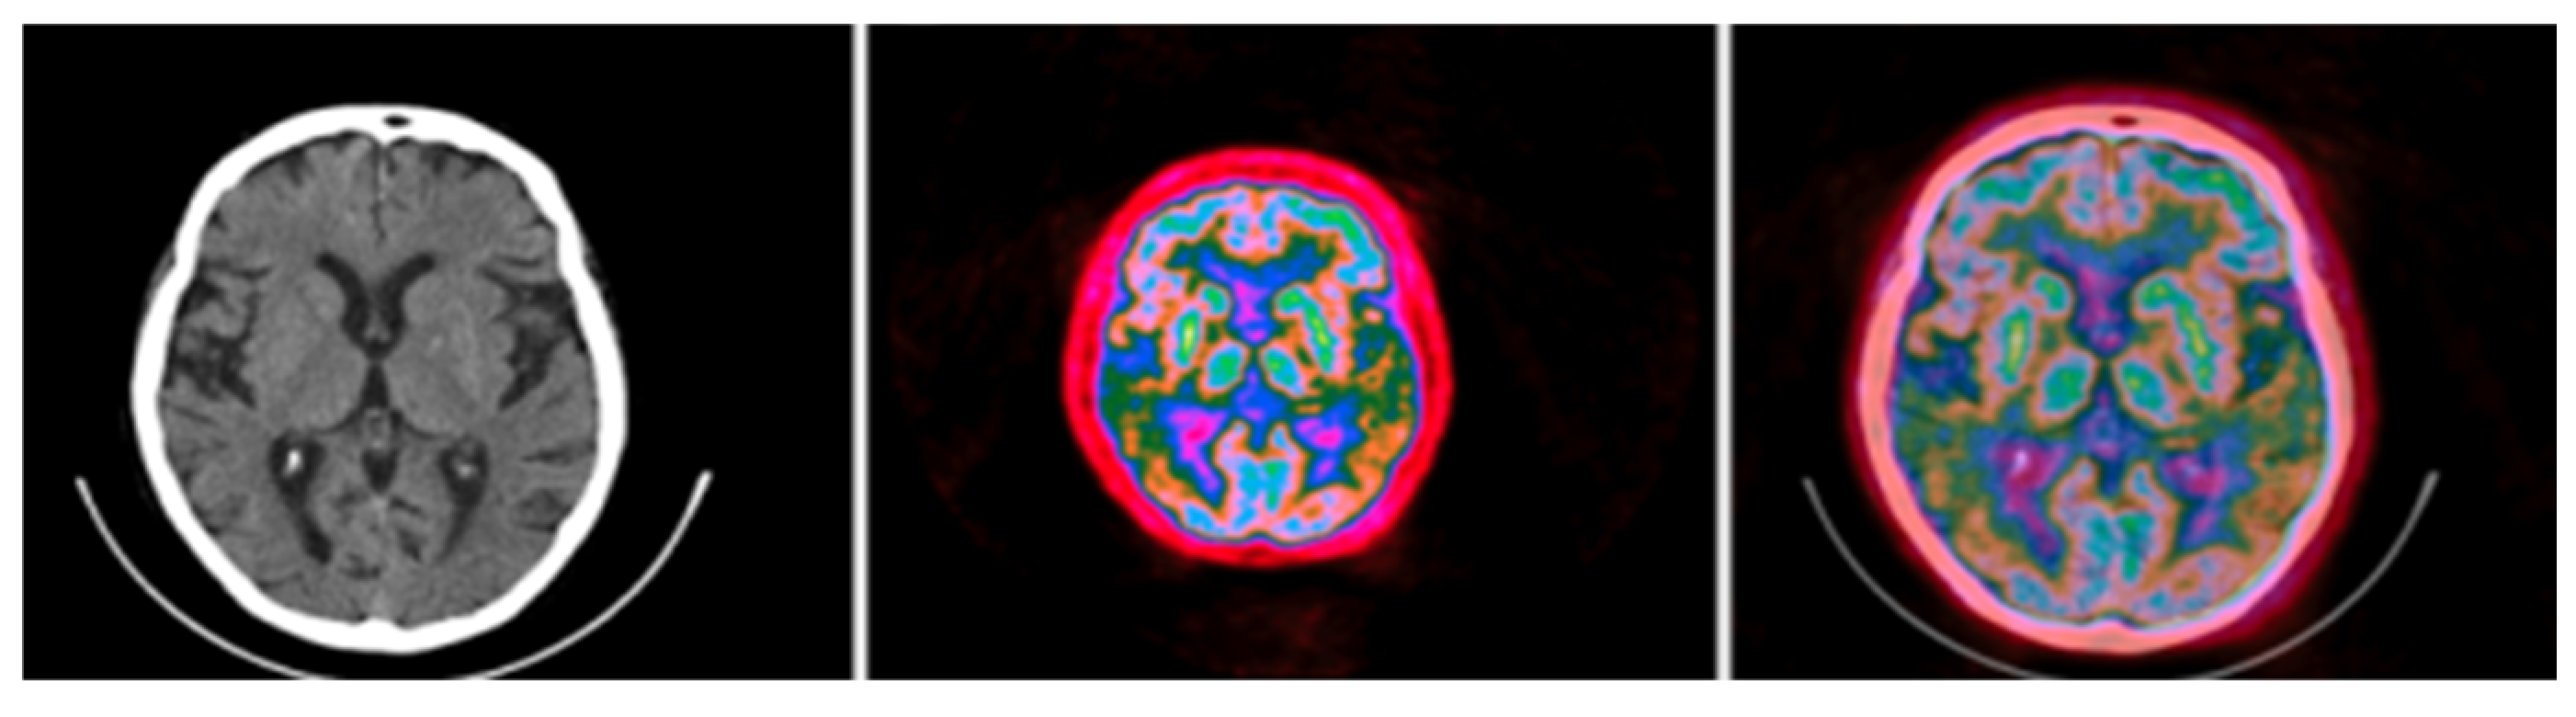

3.1. CIT Application

3.2. Colormap Folding Application